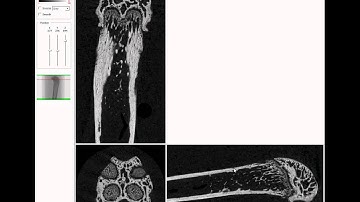

Bruker microCT tutorial: Setting the cortical VOI for the mouse femur